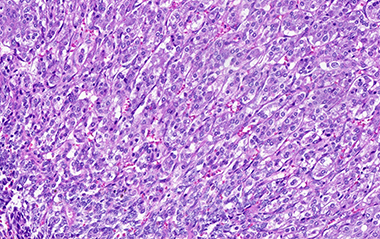

Pheochromocytoma was identified comprising 50% of tumor volume. In addition, the lesion contained a primitive round cell component possibly neuroblastoma with focal neuroblastic differentiation (20%) and a malignant peripheral nerve sheath tumor (30%) with heterologous elements (cartilage). Areas of hemorrhage and necrosis were noted resulting in cystic degeneration.

C. Pheochromocytoma with "zellballen" features

D. Pheochromocytoma